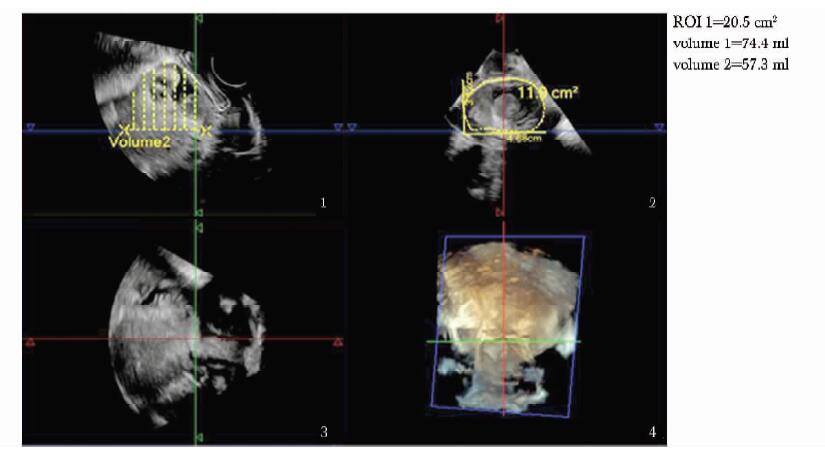

方法  收集2011年11月至2013年1月北京协和医院临床确诊为剖宫产切口瘢痕妊娠、并接受手术治疗的35例患者, 术前进行二维及三维超声检查, 获得病灶最大径、病灶平均径、病灶植入瘢痕面积、植入体积及植入深度; 按有无胎心搏动、病灶类型、彩色多普勒血流分级及术前有/无甲氨蝶呤联合治疗进行分组。记录患者手术中出血量, 分析超声参数与出血量的相关性, 比较组间出血量差异; 将病灶按出血量进行分组, ≥ 200 ml组和 < 200 ml组, 应用Logistic回归分析影响出血量的独立危险因素。

Methods  A total of 35 CSP patients who received operational treatment from November 2011 to January 2013 were enrolled in this study. The 2-and 3-dimensional ultrasound examinations were performed before the surgery, and the following parameters were recorded:maximum diameter of lesion(Dmax), average diameter of lesion(Dmean), implantation area of lesion(S), implantation volume of lesion(V), and implantation depth of lesion(Dimp). All these cases were divided into different groups according to the following characteristics separately:with/without fetal heart beat, lesion shown as gestational sac/mass, vasculature grade poor/median/rich, whetheror not combined with methotrexate(MTX) treatment prior to operations. The amount of bleeding during the operation was recorded. The correlation between the above parameters and the amount of intraoperative bleeding was analyzed. The bleeding amount of different groups was compared. Also, the patients were divided into two groups according to bleeding amount ≥ 200 ml and < 200 ml, and the potential independent risk factors of bleeding were analyzed using Logistic regression.